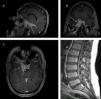

The differential diagnosis of bilateral lower extremity weakness is broad. We present a very rare case of a 48-year old male patient, with walking difficulties due to Bing–Neel syndrome. On clinical examination, there was a significant loss of muscle power in all his lower extremities key-muscle groups. The lumbar spine magnetic resonance imaging (MRI) showed only mild degenerative changes, whereas the MRI of the head indicated a diffuse meningeal thickening at the right temporal region, characterized by significant enhancement after contrast administration. Serum protein electrophoresis detected an IgM-kappa monoclonal protein. The patient received intrathecal chemotherapy with methotrexate and cytarabine, and was started on oral ibrutinib 420mg daily. In conclusion, a past medical history of Waldenstrom macroglobulinemia in conjunction with neurological manifestations should alert the treating physician for Bing–Neel syndrome. A complete diagnostic imaging and serologic protocol helps in setting the final diagnosis. Steroids are part of the treatment, but should be given after the diagnosis is set. Neurosurgical intervention is indicated for histologic confirmation in the case of diagnostic uncertainty.